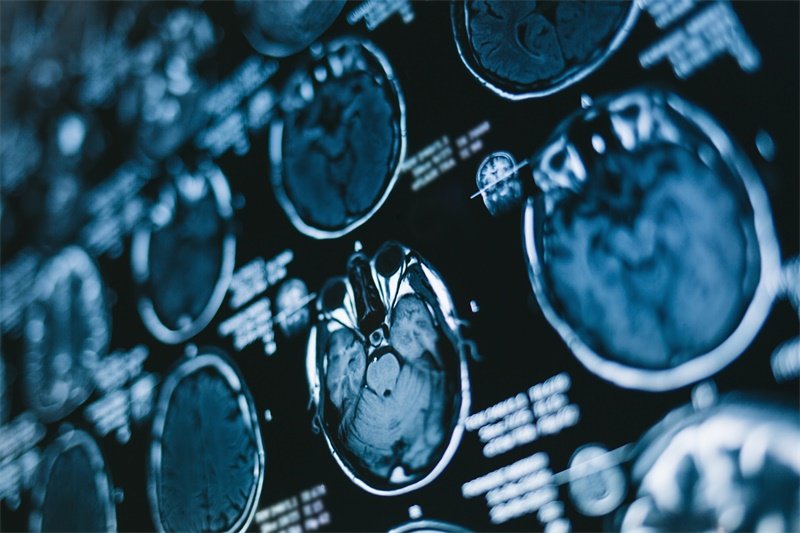

这种病变最常见的形式包括肿瘤、囊肿、血肿或其他组织增生。在影像学检查中,例如CT或MRI扫描,这些病变通常可以被很好地识别。医生会根据占位性病变的表现,制定相应的治疗方案。

最主要的诊断手段是影像学检查。MRI和CT是常用的检查方式,通过这些影像,可以清晰地看到大脑的结构及占位性病变的特点,进一步分析其可能的性质。